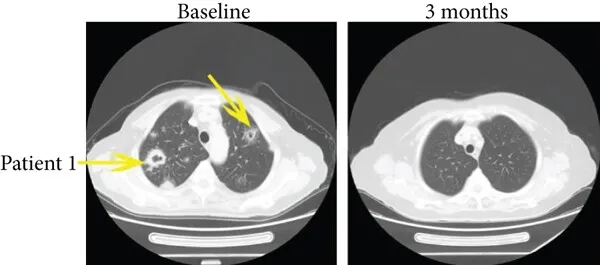

病例1是一位35岁患者,治疗前伴肺转移,患者在接受免疫治疗3个月后,多发性肺转移消失(详见下图a,黄色箭头所示),PFS达15.4个月。

▲图源“J Immunol Res”,版权归原作者所有,如无意中侵犯了知识产权,请联系我们删除